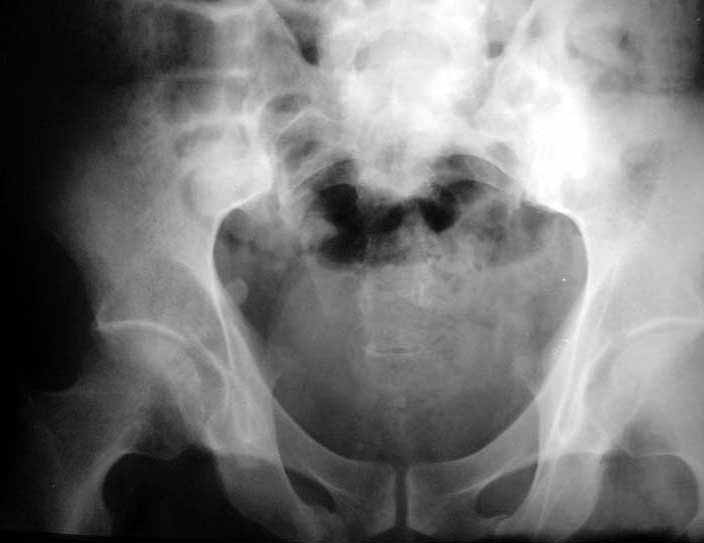

Based on the CT images you provided, he appears to have a nonunion of the the right ischium, which would explain his symptoms. General principles of treatment of hypertrophic (which this appears to be) nonunions suggest rigid fixation, but I'm not sure what the best approach would be. Could get a lag screw across the fracture through a Kocher-Langenbeck approach or plate osteosynthesis through direct ischial approach, but perhaps Chip, Adam or someone with more pelvic fracture experience could enlighten us all.

I think the cuts in question (albeit small) are on the right of the bottom row of the CT scan

I think this is just a pelvic ring disruption that has gone on to a non-union. The arrow is pointing to the inferior ramus non-union, and the sup ramus is a high "root" fracture, right near the pecten. The sup ramus fracture enters the tab - you could call it an acetabular fracture - but down here in Dallas we treat these acutely as stable pelvic ring injuries. The fracture in the anterior portion of the acetabulum is so low it doesn't seem to cause much trouble.

His R sacroiliac joint is opened anteriorly a little bit - the "unreduced posterior lesion" Alex mentioned in his first post. My earlier post about plating, bone grafting, etc., is all wrong.

What you have is a pelvic fracture that hasn't healed after 4 months or so, with a minimal deformity.